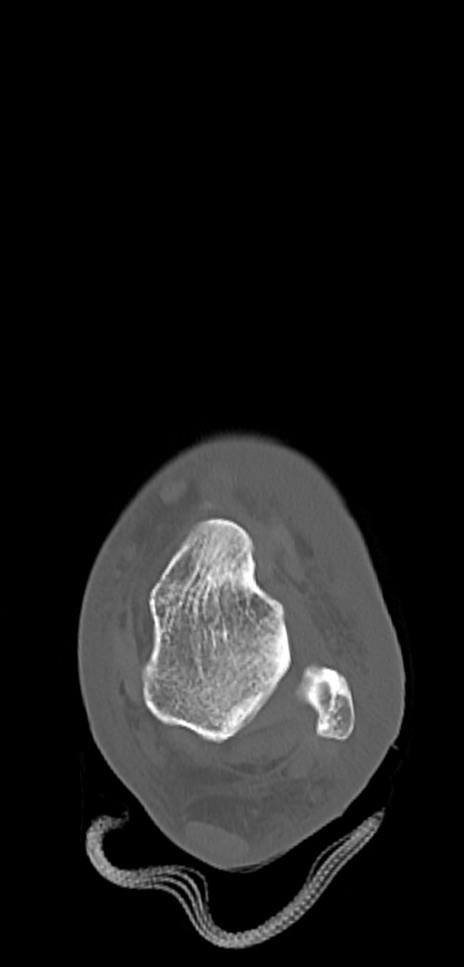

症例37 左足関節CT(横断像)

左足関節CT